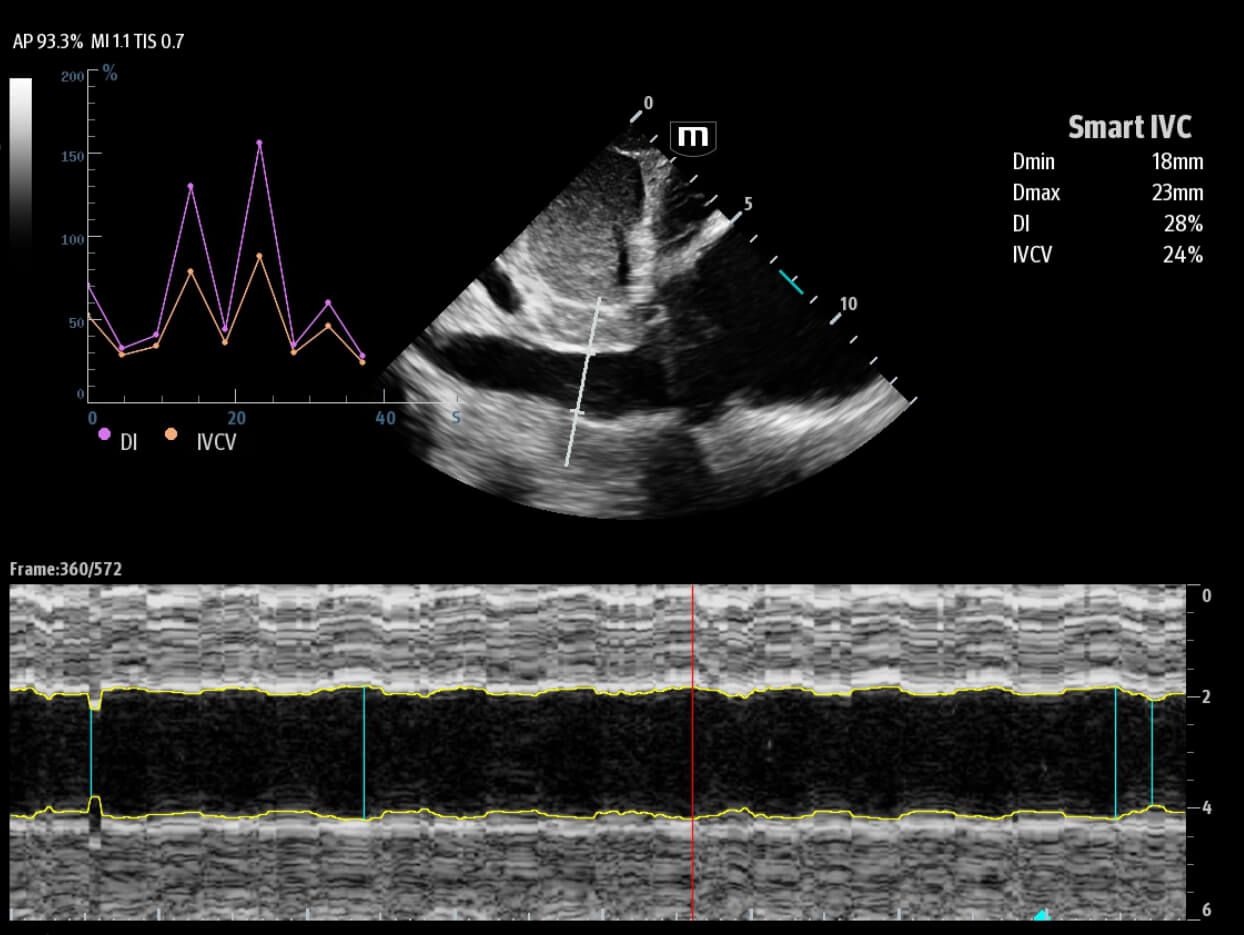

Based on the professional society guidelines for point of care ultrasound, the X-Pilot suite integrates historical diagnostic images and multi-organ data into a concise and precise view of the patient status to support rapid clinical decisions at the bedside.